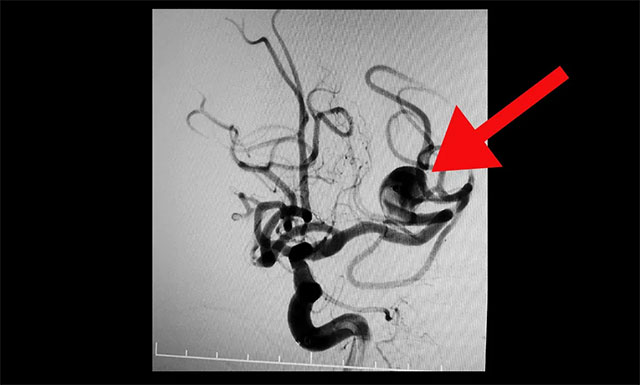

DSA檢查確診:左側大腦中動脈分叉部動脈瘤,瘤頸 6mm,瘤體 13 mm* 15 mm,屬于大型寬頸復雜動脈瘤。該動脈瘤有持續(xù)增大并有破裂風險,手術指征明確。

▲ DSA 檢查確診:左側大腦中動脈分叉部動脈瘤